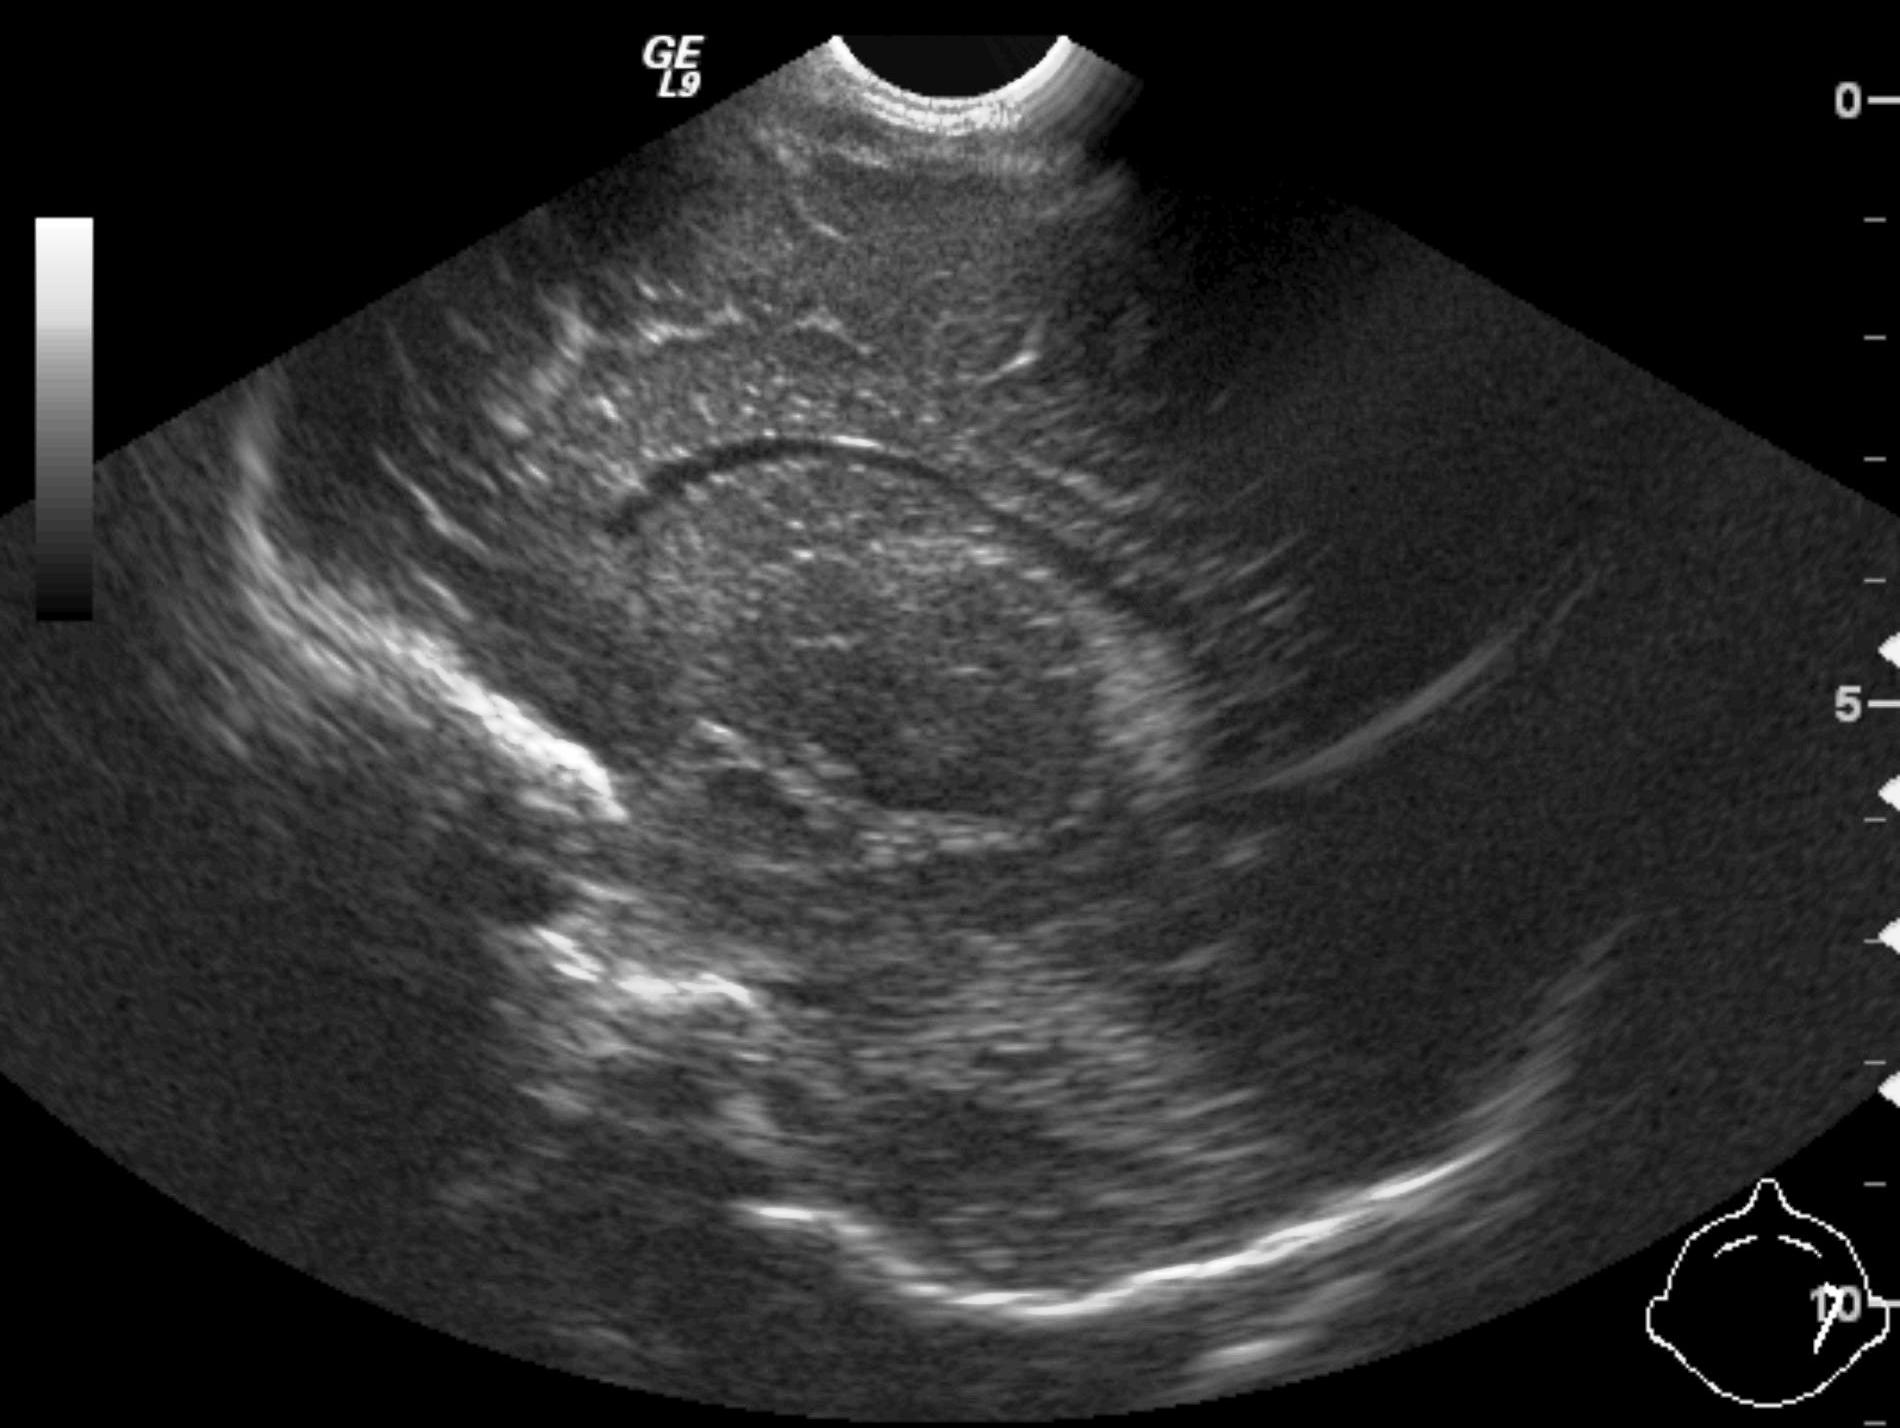

Invagination. A distal intestinal loop invaginating to a proximal intestinal loop can result in a mechanical intestinal obstruction, and cause ischemic damage. It most frequently occurs in infants (3-24 months) with recurring, colic-like complaints, distended intestines, a palpable mass and with frequent vomiting and bloody stool. Invagination requires immediate diagnosis and desinvagination. US exam reveals the invaginated intestines as a “target” sign in axial cross section and looks like a “pseudokidney” in longitudinal cross section. The therapy is hydrostatic or pneumatic desinvagination. Perforation and/or peritonitis are absolute contraindications to these procedures. Hydrostatic desinvagination can be performed under fluoroscopy or with US guidance and is considered successful if air or the contrast material appears in the terminal ileum and the invaginated loop disappears. If these efforts do not succeed, surgical desinvagination is needed.

17. “Target” sign. Invagination. .